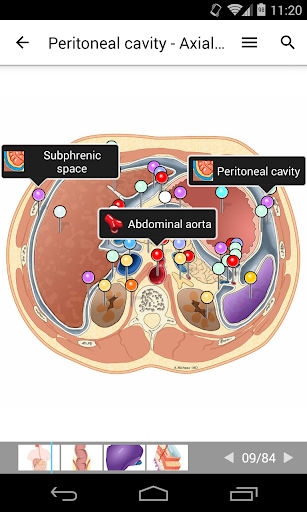

- يتميز وضع الدبابيس بسلوك جديد يسمح لك باتباع بنية تشريحية بسهولة أكبر

- ضمن عرض التفاصيل للبنية التشريحية ، يشير الدبوس الآن إلى البنية ذات الصلة في جميع الصور الحالية

انقر أيضًا مباشرة على الصورة للانتقال إلى الصورة المعروضة في تلك الوحدة

- يمكنك الآن إخفاء الهياكل واحداً تلو الآخر (زر جديد داخل نافذة الوصف المنبثقة) وعرضها مرة أخرى في القائمة الصحيحة